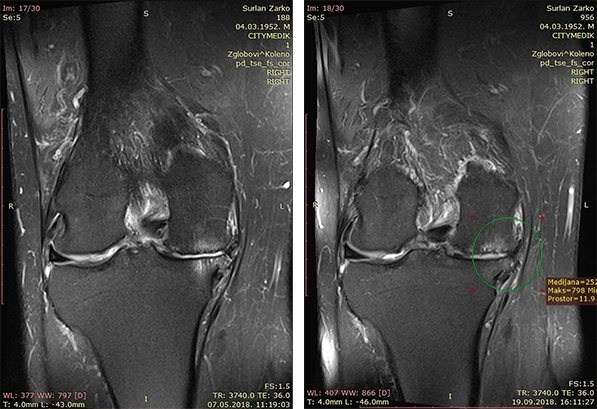

Snimci magnetnom rezonancom koji pokazuju obnavljanje i zadebljanje hrskavice kolena |

Verifikovano objektivnim dijagnostičkim postupcima (ultrazvuk, rendgen, magnetna rezonanaca), kao i merenjima prema skalama koje se uobičajeno koriste u reumatologiji (VAS, WOMAC, IKDC, KOOS), petogodišnja primena metode pokazala je njenu nedvosmislenu uspešnost: superiornija je u odnosu na sve ostale, i jedina je koja dovodi do regeneracije hrskavice kuka. U pomenutoj studiji, koju je u svom udžbeniku za regenerativnu medicinu nedavno objavila BioBridge fondacija, dr Barać navodi jedan od takvih primera, primenu BS metode kod 66-godišnjeg pacijenta sa teškim osteoartritisom oba kolena. Četiri meseca posle samo jednog ubrizgavanja mešavine matičnih ćelija iz koštane srži pacijenta i celularnog matriksa, prema BS protokolu, navedena merenja potvrdila su značajno poboljšanje po svim parametrima; snimci magnetnom rezonancom pokazali su obnavljanje i zadebljanje hrskavice kolena, uz istovremeno smanjenje koštanog edema.